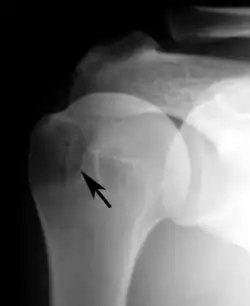

Plain x-rays of the shoulder may show a “proximal humeral pseudocyst”. This localized area of bone atrophy is the result of increased blood circulation which demineralizes the bone at the attachment of the rotator cuff tendon. It is evidence of chronic inflammation of the rotator cuff. Chronic shoulder inflammation is frequently asymptomatic, and this cystic appearance may be the only evidence of an inflammation.[22][23]